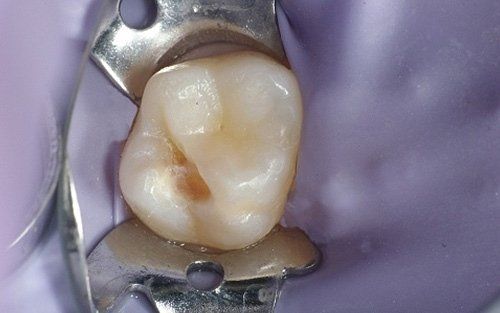

perfect disinfection and isolation of the operating field to be successfully applied. The rubber dam is a sheet of latex or silicone (some images below), invented back in 1864, available in various colours, applied to the teeth whenever treatments are carried out, whether it's a simple filling, sealant, a more complex restorative therapy (inlay and/or veneer), or endodontic therapy (root canal treatment) or adhesive cementation of a prosthetic crown. It is absolutely necessary when

old amalgam fillings need to be removed

from a tooth as it prevents the patient from ingesting the mercury contained within it. The patient, both adult and child, is

protected by the rubber dam, which prevents them from inadvertently swallowing small instruments and/or materials used by the operator during treatments.